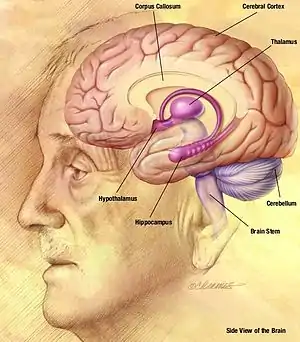

The hippocampus is a structure in the brain that has been associated with various memory functions. It is part of the limbic system, and lies next to the medial temporal lobe. It is made up of two structures, the Ammon's Horn, and the Dentate gyrus, each containing different types of cells.[1]

The cerebellum ("little brain") is a structure located at the rear of the brain, near the spinal cord. It looks like a miniature version of the cerebral cortex, in that it has a wavy, or convoluted surface.[3]

Located above the hippocampus in the medial temporal lobes are two amygdalae (singular "amygdala"). The amygdalae are associated with both emotional learning and memory, as it responds strongly to emotional stimuli, especially fear. These neurons assist in encoding emotional memories and enhancing them. This process results in emotional events being more deeply and accurately encoded into memory. Lesions to the amygdalae in monkeys have been shown to impair motivation, as well as the processing of emotions.[5]

The basal ganglia are a group of nuclei which are located in the medial temporal lobe, above the thalamus and connected to the cerebral cortex. Specifically, the basal ganglia includes the subthalamic nucleus, substantia nigra, the globus pallidus, the ventral striatum and the dorsal striatum, which consists of the putamen and the caudate nucleus.[8] The basic functions of these nuclei deal with cognition, learning, and motor control and activities. The basal ganglia are also associated with learning, memory, and unconscious memory processes, such as motor skills and implicit memory.[4] Particularly, one division within the ventral striatum, the nucleus accumbens core, is involved in the consolidation, retrieval and reconsolidation of drug memory.[9]